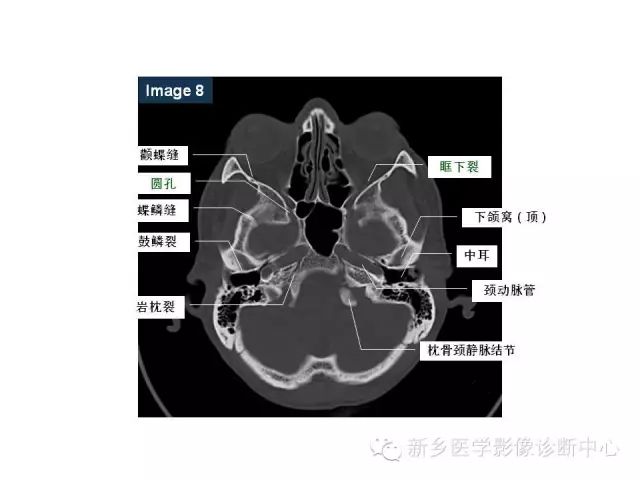

鼻咽部的详细解剖(含各个孔道)

来源:新乡医学影像诊断中心